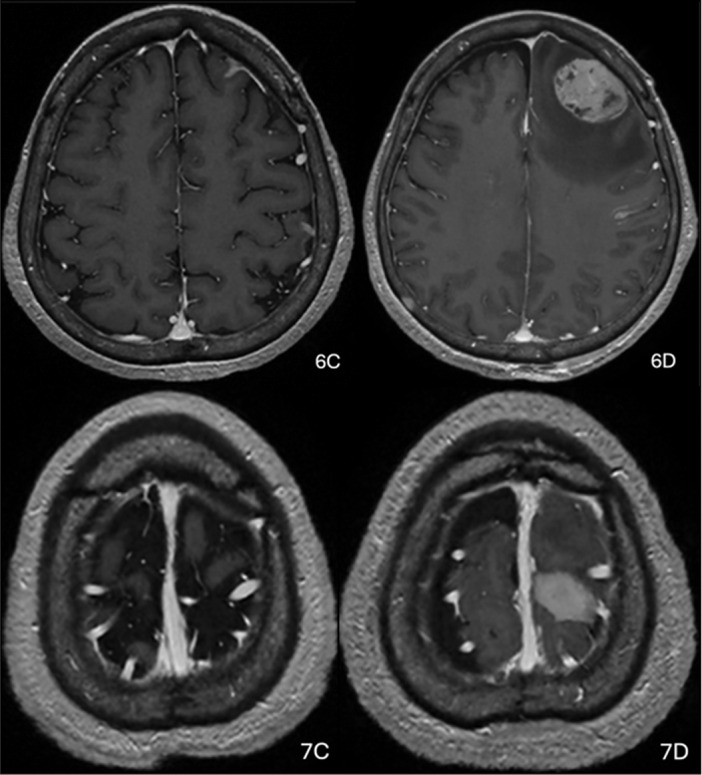

一名68岁女性,表现为进行性偏瘫和吞咽困难,最初推测为亚急性中风。连续MRI显示波动的FLAIR高强度和基底节区和皮层的强化病变,最终诊断为原发性中枢神经系统b细胞淋巴瘤。该病例强调了将临床演变与非典型神经学表现的影像学特征相结合的重要性。教学点:在FLAIR高强度波动和增强脑病变的情况下,即使没有典型的影像学特征,也应考虑原发性中枢神经系统淋巴瘤。

A 68-year-old woman presented with progressive hemiparesis and dysphagia, initially presumed to have subacute stroke. Serial MRI revealed fluctuating FLAIR hyperintensities and enhancing lesions in the basal ganglia and cortex, ultimately leading to the diagnosis of high-grade primary CNS B-cell lymphoma. The case highlights the importance of integrating clinical evolution with imaging features in atypical neurological presentations. Teaching point: In cases of fluctuating FLAIR hyperintensity and contrast-enhancing brain lesions, primary CNS lymphoma should be considered, even in the absence of typical imaging features.